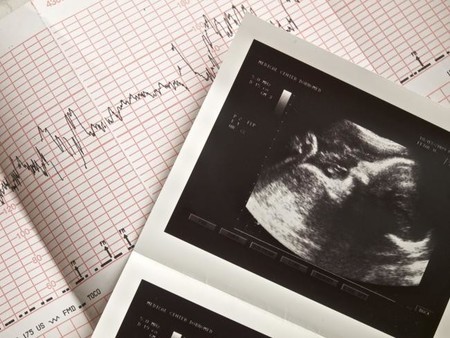

El nombre es el del ginecólogo que descubrió el método, el Dr. Saad Ramzi Ismail, quien asegura que se puede conocer el sexo del bebé incluso desde la primera ecografía con un 97% de fiabilidad aunque no se vean sus genitales.

La clave está en la posición de la placenta respecto del feto y en el emplazamiento de las vellosidades coriónicas que forman parte del tejido que conforma la placenta.

En el año 2011 publicó un estudio en el sitio web ObGyn.net con los resultados basados en la observación de las ecografías realizadas a más de 5.376 embarazadas, de las cuales a un 22 por ciento se le practicó una ecografía transvaginal a las 6 semanas de gestación.

Encontró que el 97,2 por ciento de los niños presentaba la placenta o las vellosidades coriónicas (tejido que colabora en la formación de la placenta) en el lado derecho del útero, mientras que el 97,5 por ciento de las niñas la tenían a la izquierda.

Más tarde, entre las semanas 18 y 20 de gestación, mediante ecografía transabdominal se confirmó el sexo de los bebés en un 98-99 por ciento de los casos, ratificando lo que se había observado semanas antes.

La lateralización indicada por el Dr. Ramzi se interpretaría en el caso de ecografías transvaginales, ya que en el caso de ecografías transabdominales la ubicación de la placenta, que se identifica como una zona brillante, debería interpretarse en espejo.